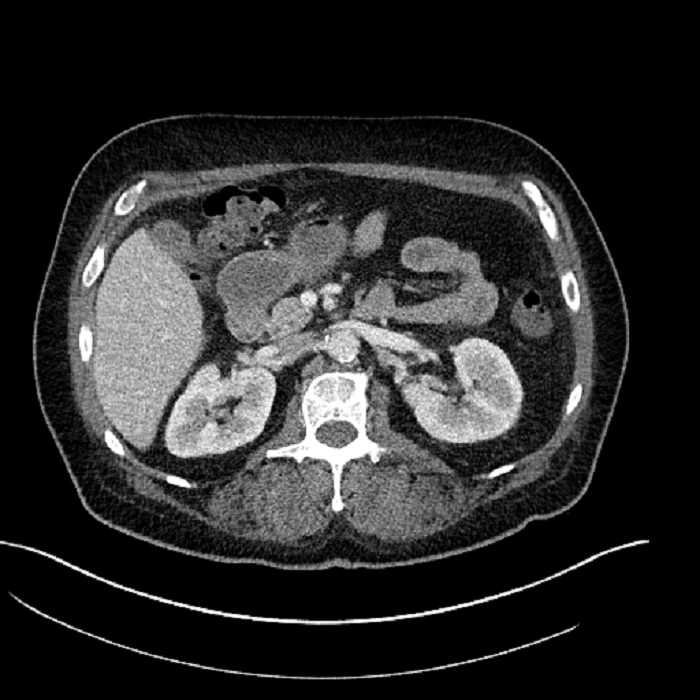

• Large fluid density structure in hepatic segments 7 and 8 measuring 10 x 7 x 7 cm with internal septation and circumferential ill-defined low density compatible with edema

• Peripherally enhancing subcapsular collections along the anterior margin of the left hepatic lobe measuring 3 x 1 cm and 2 x 1 cm

• Clearly marginated fluid density structure in segment 7 and several other scattered tiny hypodensities, which likely represent cysts

• Hepatic abscess

Acute sigmoid diverticulitis complicated by a small contained perforation and a large abscess in the right hepatic lobe. Additional small subcapsular abscesses along the anterior margin of the left hepatic lobe.

• The classic CT imaging appearance is a double target sign with internal low density surrounded by an internal enhancing rim (capsule) and a low density external rim (edema)

Hepatic abscess showing the double target sign with low density internally surrounded by a thin inner enhancing rim (red arrow) and ill-defined outer low density rim (yellow arrow). Blue arrow indicates an internal septation. Red arrows: additional smaller subcapsular abscesses. Red arrow: focal contained perforation associated with diverticulitis.